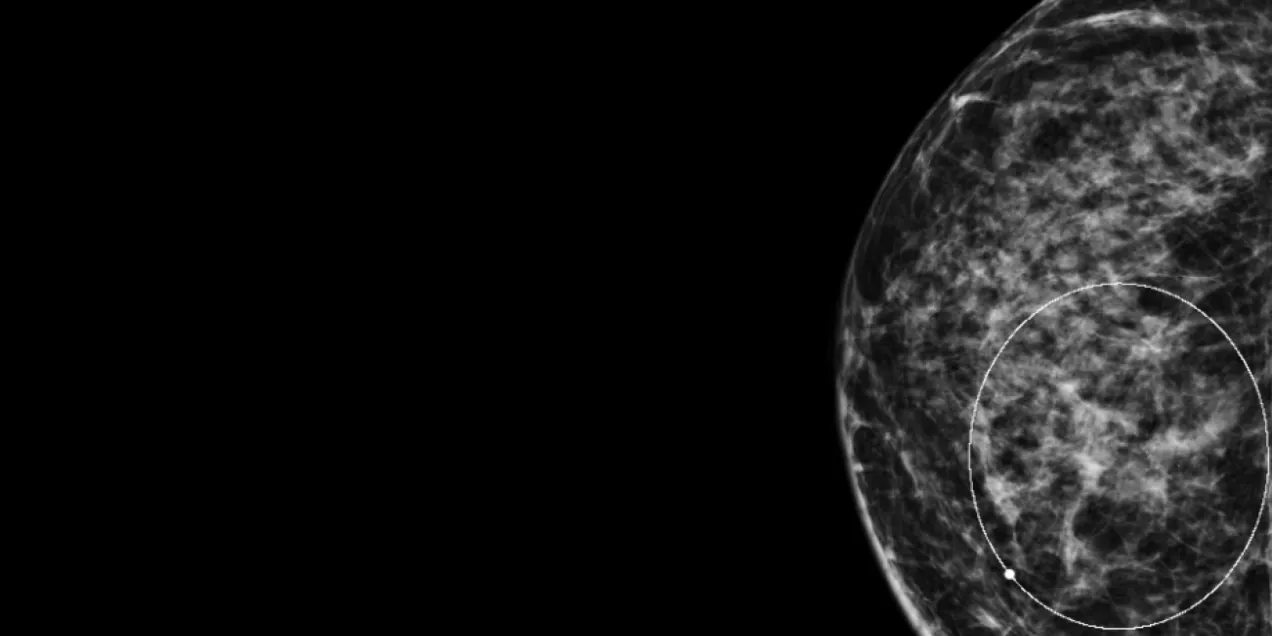

Mammogram image of the right breast showing dense breast tissue with a circular marking highlighting an area of interest.

Today, most radiology practices in the U.S. now use digital mammography because, compared to analog film, it provides better quality images with improved tissue contrast. Studies have shown that digital mammography is particularly better than film mammography for dense breasts, as well as for younger patients, who tend to have denser breast than older patients. Digital mammography also has the added benefit of lower radiation dose compared to traditional analog mammography.